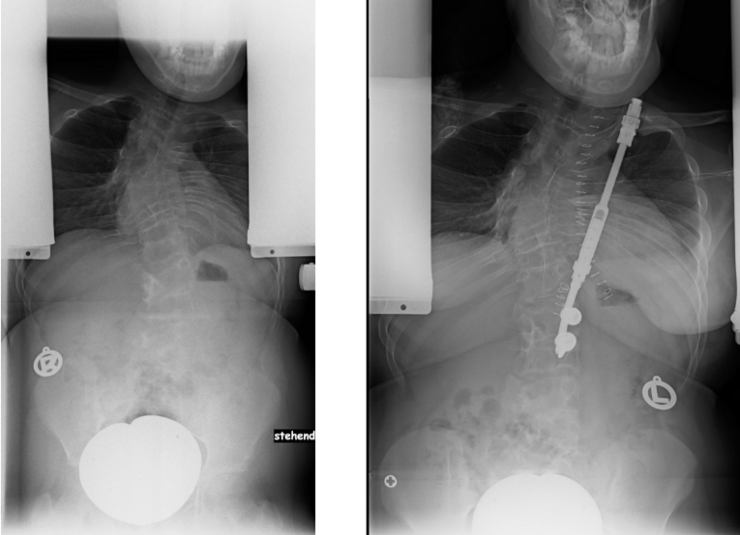

45 jährige Frau mit alter idiopathischer Skoliose

Magec-Stäbe

Die Magnetstäbe (Magec Stäbe, engl. Magec rods) werden nur oben und unten an der Wirbelsäule fixiert und dann in die Länge gezogen - ähnlich, wie das früher mit den Harrington Stäben erfolgte. 2 bis 4mal im Jahr wird über einen Magneten der Stab um einige Millimeter verlängert, bis die erforderliche Größe erreicht ist. Anschließend wird er wieder entfernt und eine konventionelle Spondylodese und Korrektur durchgeführt.

Magec rods: Beispielverlauf mit Wachstumsstäben

Der Wachstumsstab dient also vor allem dazu, die Zeit bis zur endgültigen Skoliose-Operation zu überbrücken, wenn eine Korsettversorgung nicht ausreichend ist. Auch wenn der Knochen noch nicht fusioniert (versteift) wird, ist man damit nicht beweglicher. In dem Bereich, in dem der Stab angebracht ist, ist die Wirbelsäule komplett unbeweglich. Die OP-Strecke ist in der Regel länger als bei den modernen Fusionsverfahren und da immer die Gefahr der Stablockerung oder des Stab-Bruchs besteht, ist man sportlich sehr eingeschränkt. Manchmal kommt es sogar zu einer spontanen Fusion der Wirbelsegmente allein durch die Ruhigstellung. Daher wird diese OP-Methode nur empfohlen, wenn eine Korsettbehandlung nicht möglich und die Patientinnen und Patienten für die endgültige OP noch deutlich zu jung sind. Für viele sehr junge Patientinnen und Patienten sind die Magnetstäbe die einzige Möglichkeit.